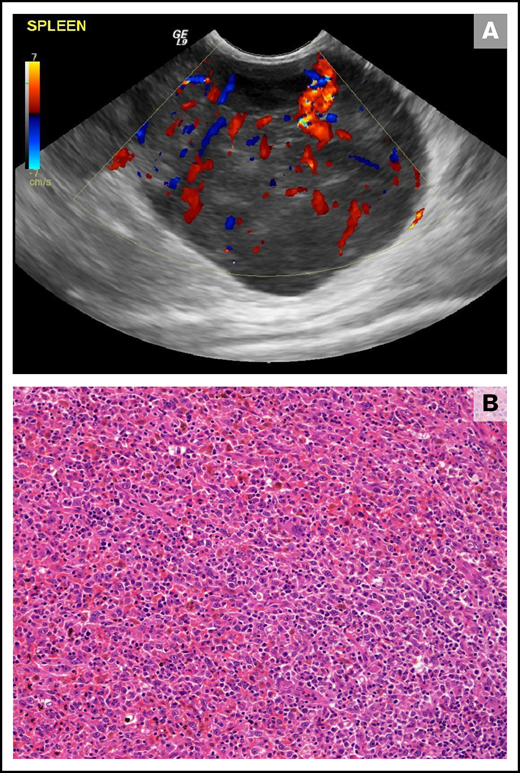

Splenic HS in a 10-year-old female neutered cross-breed dog. (A) Ultrasonographic still of a large (maximum diameter, 59 mm) well-vascularized (as demonstrated by Doppler color flow) mass lesion of mixed echogenicity within the tail of the spleen. (B) Histopathology of the splenic mass revealed a poorly encapsulated neoplasm showing both round and spindle morphologies of large tumor cells forming sheets and streams. Diagnosis of HS was confirmed using immunohistochemical stains (not shown; hematoxylin and eosin stain; ×20 objective).